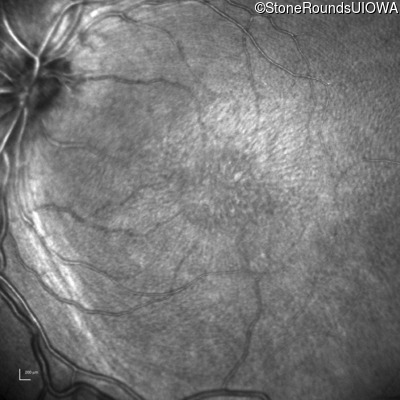

Infrared Fundus Photograph - Right - 10/40

Exemplar